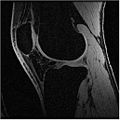

Multi-Contrast MR Approach

In this algorithm, we try to collect MR images of Knee using different MR scans like IDEAL-SPGR-FAT, IDEAL-SPGR-WATER, IDEAL-GRE-FAT etc. The main assumption in this algorithm is that different structures of interest ( eg: bones/cartilage) have different intensity values in different scans. For eg: Bones are colored with lower pixel intensity values in IDEAL-SPGR-WATER dataset whereas they are colored with higher pixel intensity values in IDEAL-SPGR-WATER dataset.

Firstly, we collect the seed points of the regions of interest using an insight application "ImageViewer". So each file with the seed points is considered as one cluster. For eg: we can have clusters for background, bones, cartilage etc. Next, we calculate the cluster centers (µ) and standard deviation (ρ) for each seed file. We try to define user defined parameter called numberOfSd(α) which represents the extent of how far a cluster can go. The numberofSd(α) has been split to be bi-directional in the x-axis representing one contrast image and y-axis representing another contrast image.

Below is the dataset of Knee MR image we used

We have also proved that our algorithm works fairly well for hip dataset. Below are the MR images of Hip dataset we used.

The segmented output we got using our approach is